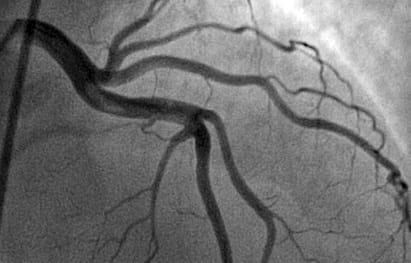

Коронарография представляет собой малотравматичное исследование коронарных артерий сердца, в ходе которого вводится контрастное вещество. Данное вещество становится видимым на специализированном ангиографе под воздействием рентгеновского излучения, что позволяет оценить состояние артерий и выявить участки их сужения.

Коронарография выполняется в рентгеноперационной, где осуществляется контрастирование коронарных артерий под контролем рентгена для оценки состояния коронарной системы и предсказания результатов у пациентов с ИБС.

Коронарография является наиболее информативной методикой для анализа состояния коронарных артерий. Это малотравматичная и безопасная процедура, которая на сегодняшний день считается «золотым стандартом» для выявления атеросклеротических изменений в сосудах сердца и постановки диагноза ишемической болезни сердца. Через коронарографию специалист точно определяет, на каком участке и насколько сильно сужены артерии, а также какие риски существуют для пациента. В АО «Медицина» коронарографию проводят опытные сердечно-сосудистые хирурги в рентгеноперационной, оснащенной ангиографом последнего поколения GE Healthcare Innova IGS 530. Процедура безопасна, безболезненна и не требует какого-либо обширного вмешательства, поэтому восстановление занимает минимальное время.

Специалисты оценивают различные характеристики сосудов: их толщину, длину и ширину. При необходимости выявляются также уплотнения и затемнения в тканях. Нарушения четкости и размытости границ сосудов являются тревожными признаками, а также неправильное расположение сосудов может свидетельствовать о наличии патологии.

Катетер представляет собой тонкую трубку, которую врач аккуратно продвигает к артериальному устью, контролируя процесс с помощью специального оборудования. Как только устье артерии достигнуто, через катетер вводится контрастное вещество, позволяющее получить визуализацию сосудов сердца. Во время этого процесса делаются рентгеновские снимки и видеозапись того, как вещество заполняет сосуды. Как пациент, так и врач могут следить за происходящим на мониторе. После завершения съемки врач удаляет катетер и накладывает давящую повязку на место прокола.